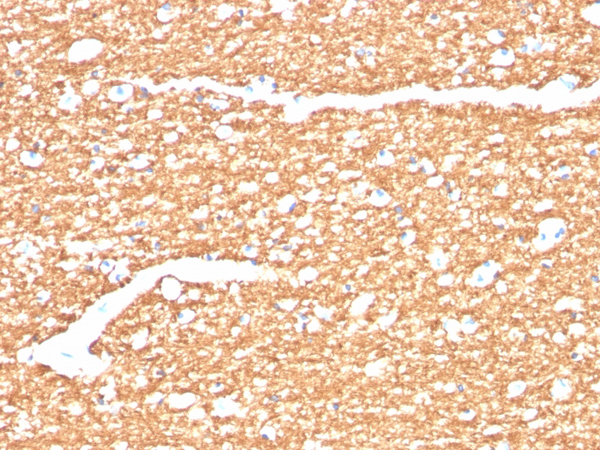

(Formalin-fixed, paraffin-embedded human brain stained with Myelin Basic Protein Recombinant Rabbit Antibody (MBP/4277R).)